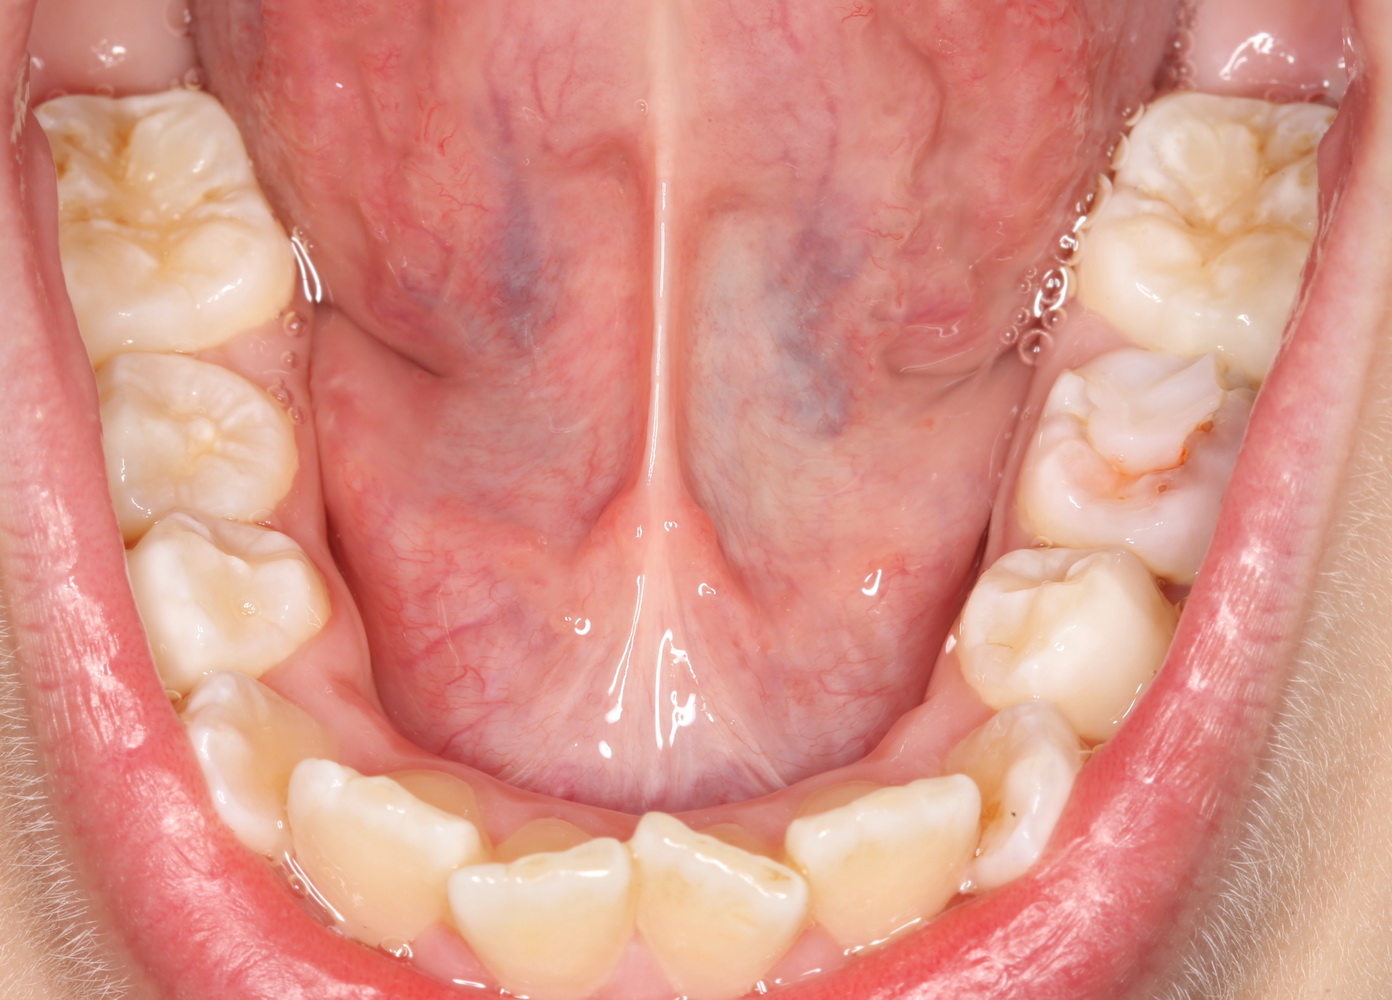

Такую работу я покажу на примере. Ко мне обратилась маленькая пациентка, девочка восьми лет с жалобами на появление новообразования под языком:

До этого они с мамой уже побывали в крупном государственном лечебном учреждении, где им поставили диагноз «ранула» и, по старой советской традиции, направили на госпитализацию и кучу анализов. Еще попутно напугали всякими страшилками, вроде того, что написал про инфекцию выше. В общем, мама девочки задумалась и обратилась ко мне.